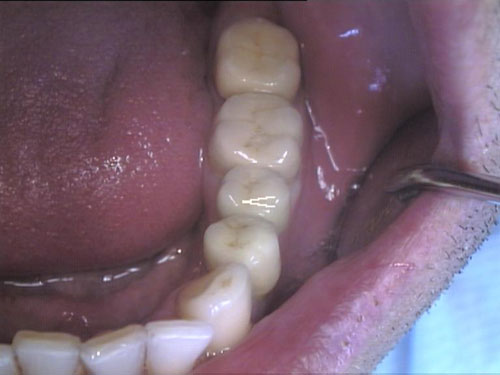

Keramikkrone 1

Keramikkrone 2